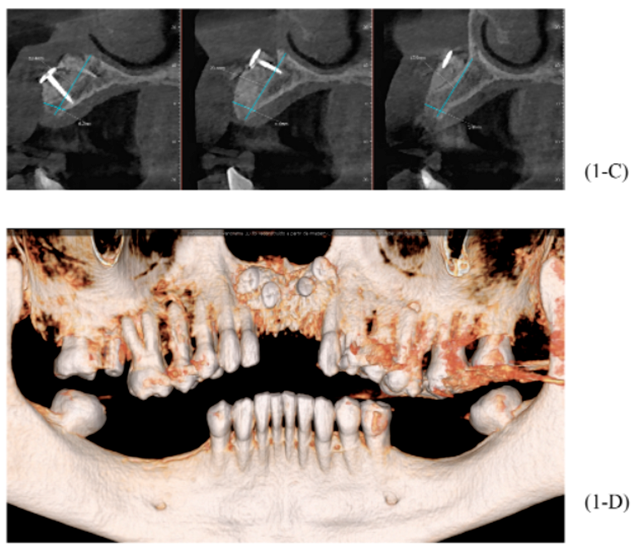

Após oito meses, foi realizada outra tomografia computadorizada (TC) na própria clínica escola, onde foram realizadas medidas de altura e espessura evidenciando grande ganho ósseo horizontal. Não ocorreu quaisquer tipo de complicação no pós-operatório tardio (imagens 1-A, 1-B, 1-C, 1-D).

Foram planejados três implantes do tipo Cone Morse Maestro Implacil De Bortoli 3.5 x 13 mm. Após remoção de maneira facilitada dos parafusos tenda, foram instalados três implantes em ótimo posicionamento tridimensional (imagens 1-E, 1-F, 1-G, 1-H). Todos apresentaram estabilidade primária de 35 Ncm de torque e aguardamos quatro meses para posterior reabilitação protética definitiva com próteses individualizadas de metalocerâmica do tipo parafusada.